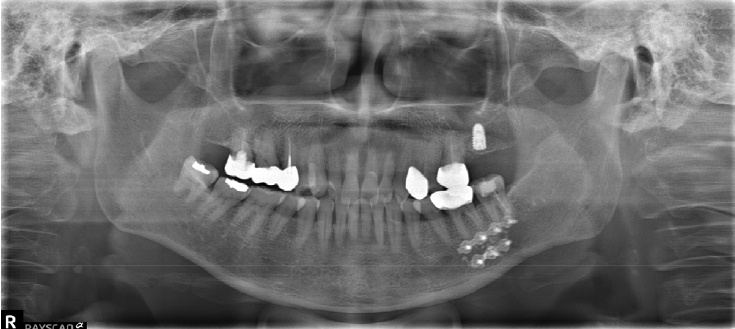

Clinical trial of platelet rich fibrin insertion for exposed dental pulp of second molar associated with impacted third molar: A pilot study

Yeeun Jo, Sanghuem Cho, Woong Nam

J Korean Dent Assoc.

2025;63(9):298-303. Published online September 30, 2025

DOI:

https://doi.org/10.22974/jkda.2025.63.9.003